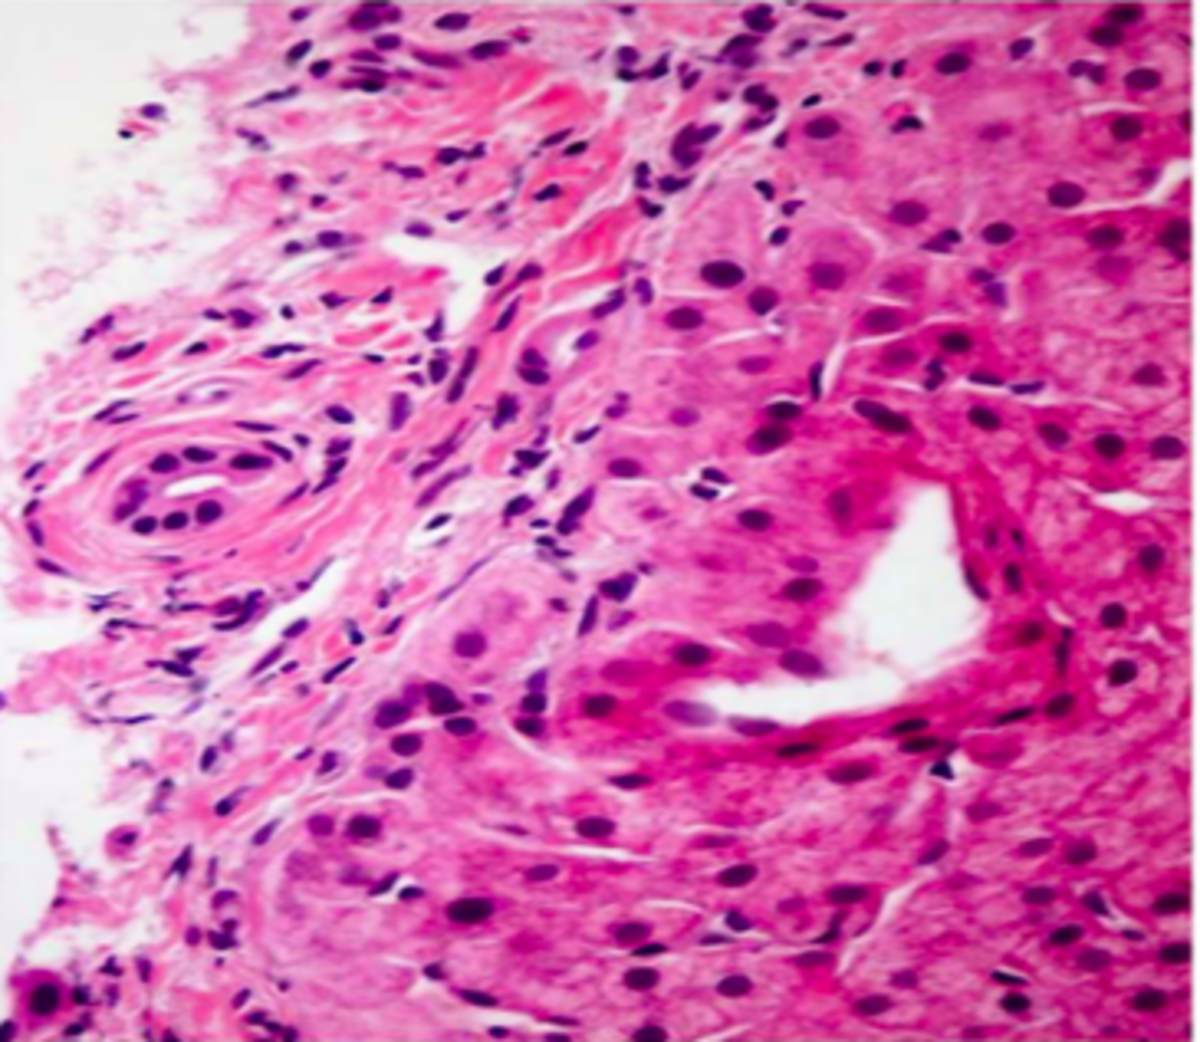

Due to the diagnostic uncertainty of the condition, a liver biopsy was performed. There was minimal steatosis (less than 5%) without evidence of interface activity. There was no evidence of granulomatous inflammation in the liver. In the portal tracts, there was evidence of bile duct loss in multiple portal tracts. In portal tracts with representative bile ductules, there was evidence of sclerosis. There was no evidence of ductulitis and no neutrophils were present in the portal tracts. IgG4 staining was performed and negative. A representative section of the biopsy is seen in the figure. What is the most likely explanation for his current liver injury?

In all patients with elevated liver enzymes, a full serological workup should be obtained. In patients with cholestatic elevations in alkaline phosphatase, a confirmatory test should be done to ensure the elevation is biliary in origin with either a gamma glutamyl transferase or 5’ nuclotidase. If the elevation is confirmed to be biliary in origin, then an imaging test is warranted as the most common cause of cholestatic elevations in liver injury tests is biliary disease. In patients with negative imaging, a liver biopsy could be considered to discover an etiology. In this case, the biopsy would be consistent with small duct primary sclerosing cholangitis.